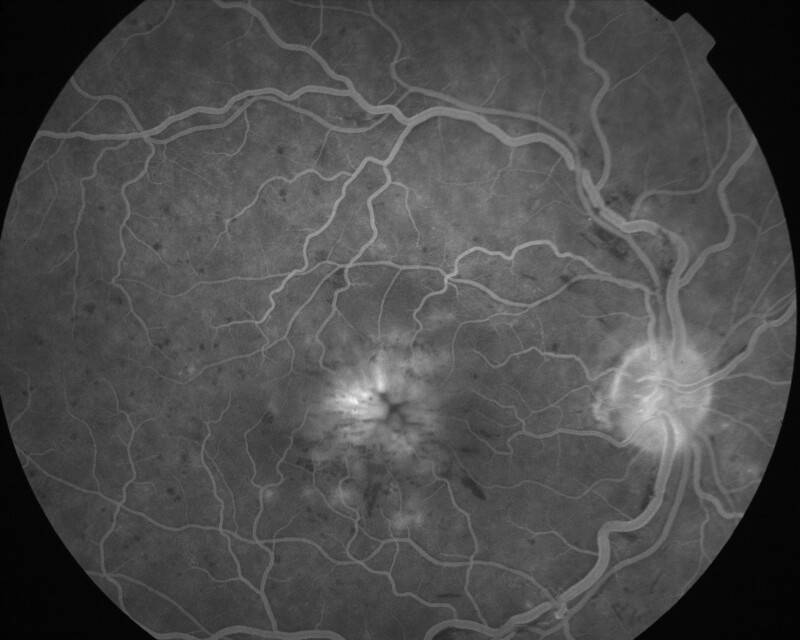

2002060602\16-09-2002